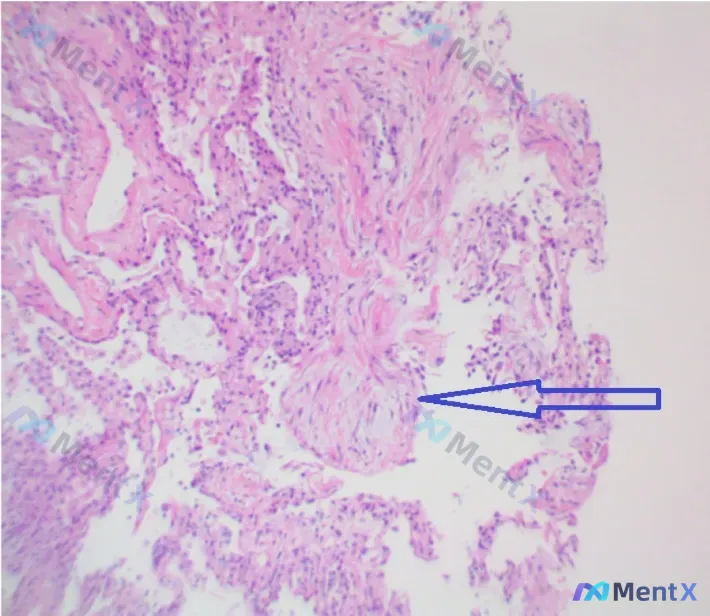

整理了一份很适合复盘点的病理读片病例: - 先看HE染色(100x):视野里是大量梭形细胞、粉色胶原束,当时第一反应很容易往「良性纤维组织增生/纤维瘤」那边靠? - 但用户补充了一个关键定位:这个结构是在肺泡腔内的,而且是「纤维母细胞栓子」——也就是Masson小体。 这个点一出来,整个诊断方向应该...